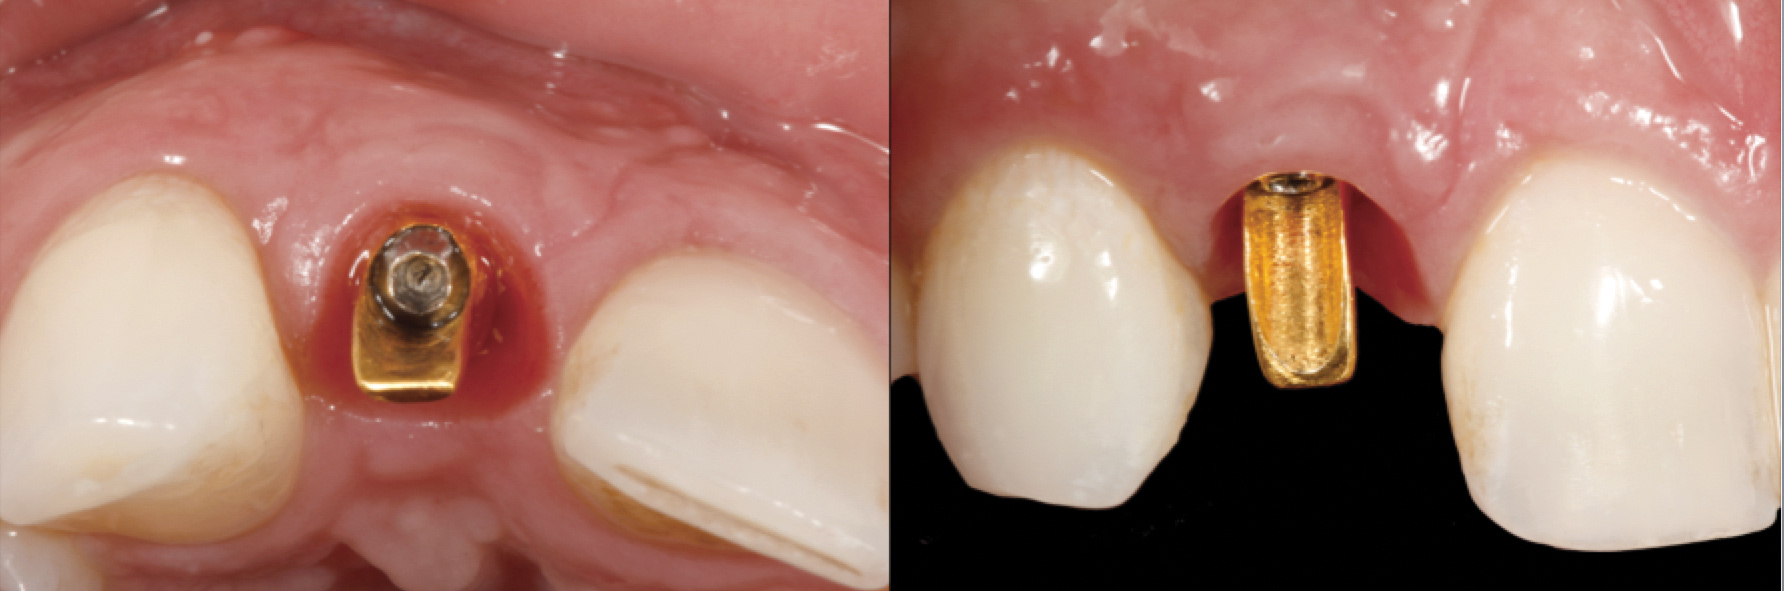

Fig 33. Excessive facial angulation of the implant placement shown with an abutment driver in the access screw hole.

Figure 33

Fig 34. A surgical cover screw was placed in an attempt to decoronate the implant and gain soft-tissue coverage in situ.

Figure 34

The following case report provides an example of this case scenario: A 24-year-old white male presented with congenitally missing tooth No. 26 restored with a single-tooth cement-retained implant restoration. The implant was placed excessively to the facial aspect of the edentulous site and too shallow, and the periodontal phenotype was thin scalloped (Figure 32). In an effort to mimic the lost midfacial soft tissues, pink ceramics were used as a cosmetic facade. Even though the restoration was not in the esthetic zone, the patient was highly displeased with the esthetic outcome and sought remediation.

The crown and screw-retained custom abutment were removed, and a surgical cover screw was placed into the implant, thereby allowing spontaneous gingival augmentation in situ (Figure 33 and Figure 34). Note that the lingual aspect of the implant site was significantly more coronal than the labial aspect, which was positive because the defect would be limited to a facial–lingual defect. A fixed RBR bridge was cemented on the adjacent teeth and used as a tooth-supported transitional provisional restoration (Figure 35). A few weeks were allotted to let the soft tissue heal and migrate around the cover screw (Figure 36) to see if there would be complete coverage, thereby allowing a soft-tissue augmentation procedure to be performed with primary flap closure as in clinical scenario No. 2. The major obstacle in achieving a positive tissue response was that the implant depth was also deficient because the implant–abutment connection was at the level of the free gingival margin. It was decided that the best treatment option would be to remove the implant. A high-powered reverse-torque device (Fixture Remover Kit, NeoBiotech, www.neobiotechus.com) was used to remove the implant atraumatically (Figure 38 through Figure 41). The implant socket was allowed to heal for several months not unlike an extracted tooth (Figure 42). A new implant was placed in a better position from both a restorative and esthetic perspective (Figure 43), and after a few months of healing, a new crown was made (Figure 44). A satisfactory functional and esthetic result was achieved (Figure 45 and Figure 46) without employing pink porcelain.